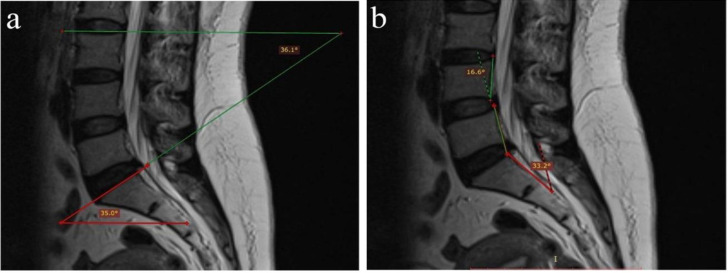

Methods: We recruited 220 patients referring to our hospital for routine lumbar MRI during 2020-2021. All the participants were subject to routine sagittal lumbar MRI, whole spine localizer scan, and coronal MRI to numerate lumbar vertebrae. Five vertebral angles (A, B, C, D, and delta) and dehydration in L4-L5 and L5-S1 discs were assessed in sagittal MRI scans. Data were analyzed using SPSS 26.

Results: Out of 220 participants (mean age: 44.29 ± 14.14 years), 36 (16.36%) were diagnosed with LSTV. Among those diagnosed with LSTV, L5-S1 dehydration was less frequently observed compared to other participants (P < 0.001). Multivariate regression showed that dehydrated L4-L5 disc, non-dehydrated L5-S1 disc, increased A-angle, and decreased D-angle can independently predict LSTV. The median A-angle was significantly larger in LSTV patients than in non-LSTV participants (P = 0.038), while the medians of C-angle, D-angle, and delta-angle were significantly smaller in the LSTV group (P < 0.05). A C-angle ≤ 35.5˚ could diagnose LSTV with sensitivity and specificity of 72.2% and 57.6%, respectively. A delta angle ≤ 8.5˚ could diagnose type 2 LSTV with 92.3% sensitivity and 87.9% specificity.

Conclusion: Measuring lumbosacral vertebral angles, especially delta-angle, in routine sagittal MRI can potentially alert physicians of a likely LSTV diagnosis.